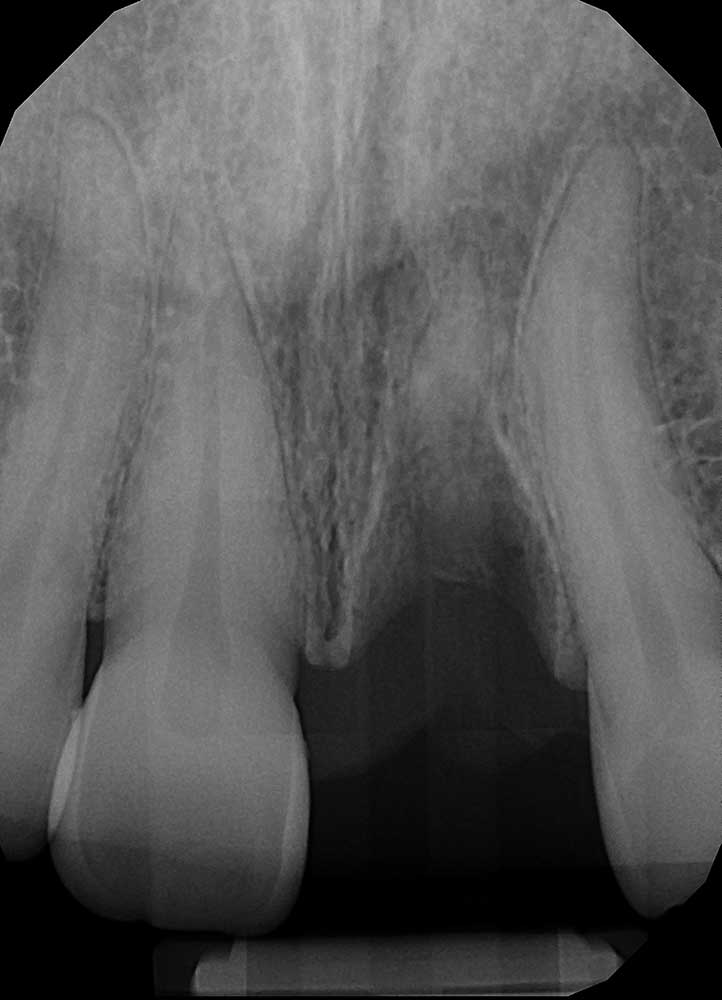

Missing Tooth

X-Ray showing missing Tooth